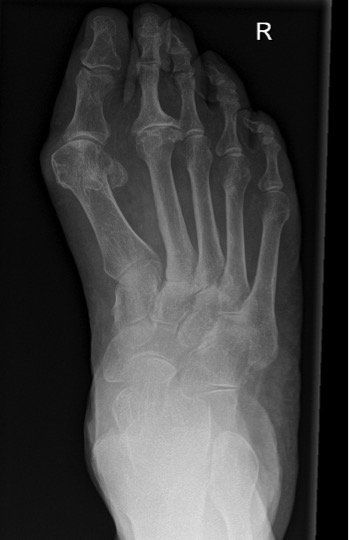

Fußchirurgie

Die häufigsten Fußerkrankungen sind der Hallux valgus, Hallux rigidus und Hammerzehen.